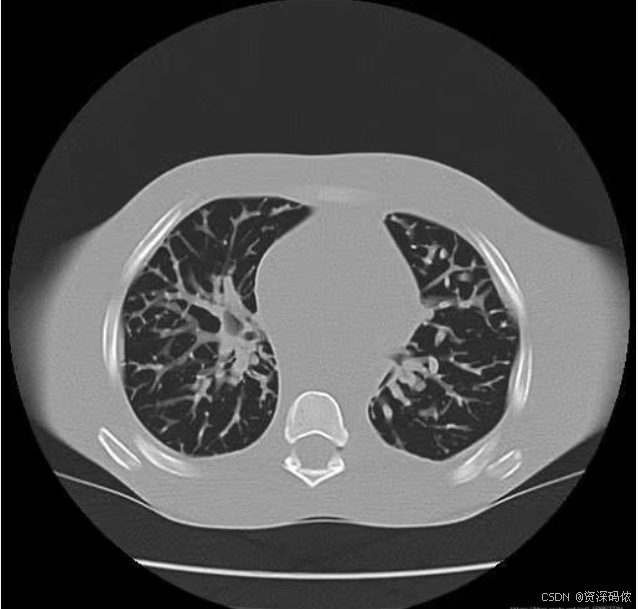

基于matlab分水岭分割算法进行图像分割

理论基础:灰度化形态学处理二值化梯度图像,然后使用分水岭分割算法提取出目标区域。

分水岭分割算法是一种经典的图像分割方法,尤其适用于处理具有明显边界信息的图像。它通过模拟地形学中的“水位上升”过程来分割图像,将图像视为地形图,其中像素值代表海拔高度。以下是基于MATLAB实现分水岭分割的完整代码示例,包括灰度化、形态学处理、二值化和梯度图像的生成。